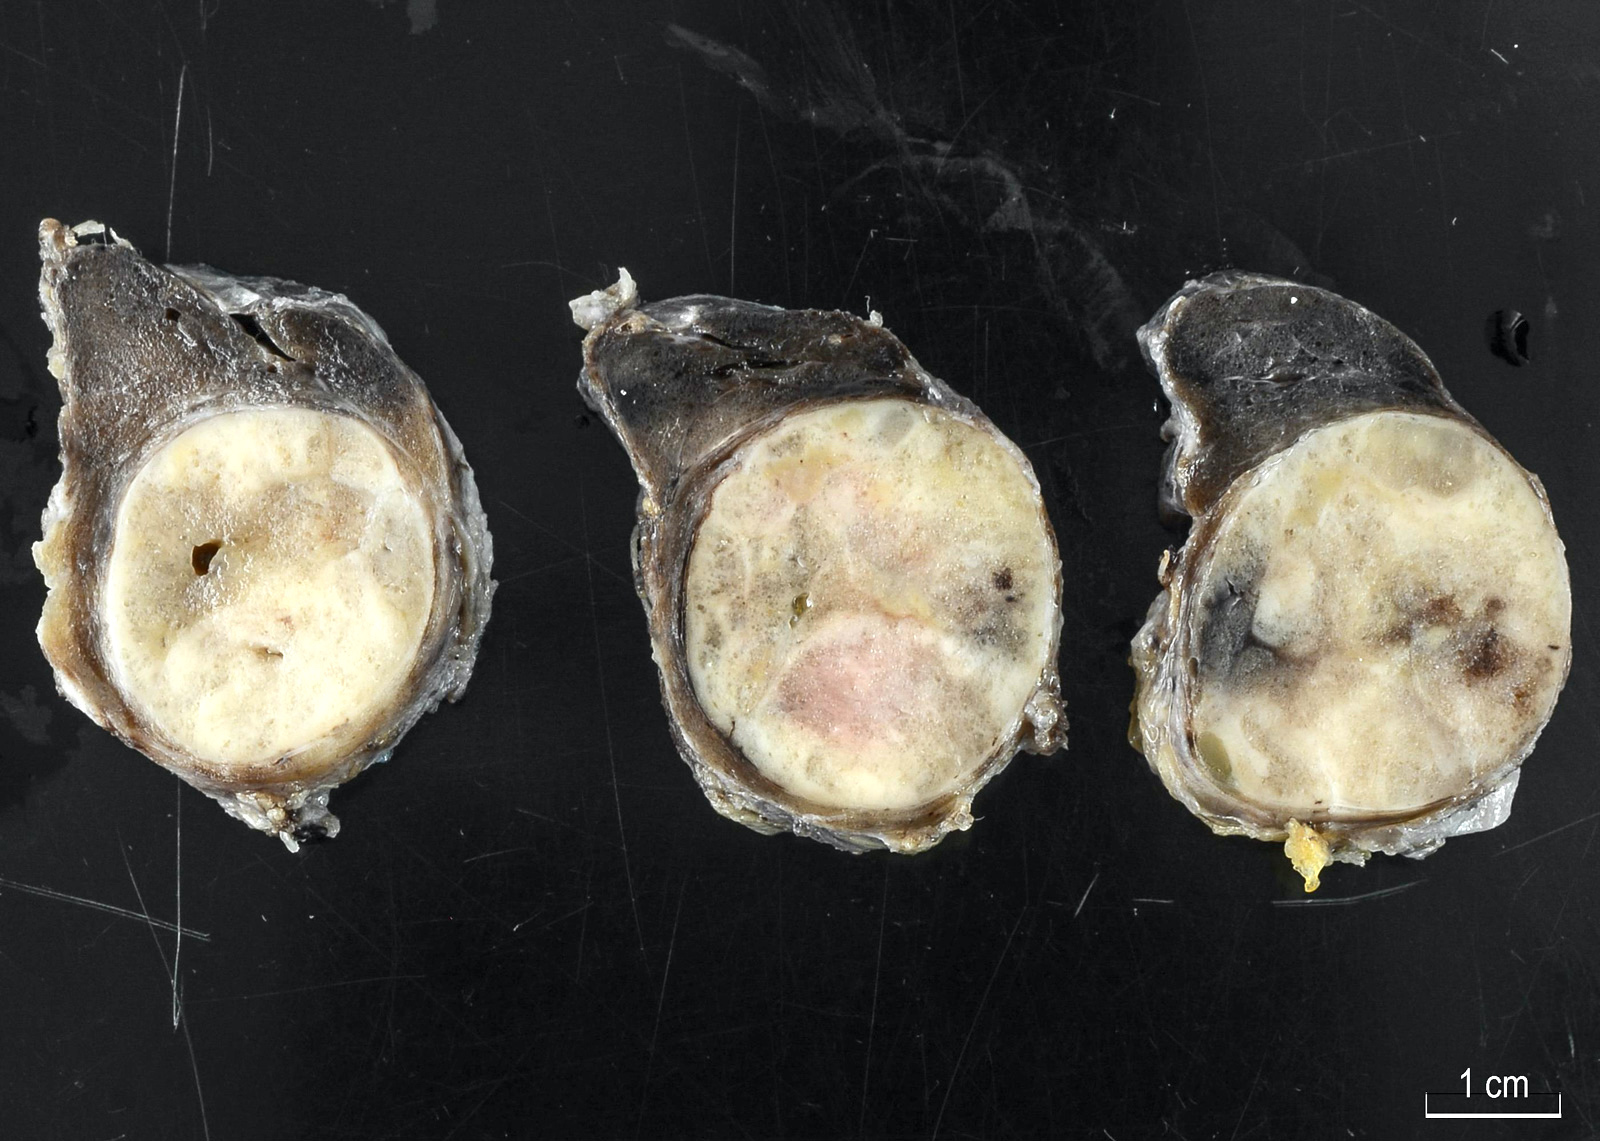

Gross description

- Solitary, encapsulated nodule; multiple if familial

- Variable size (1 - 10 cm)

- Solid, gray-white, tan to light brown

- Secondary changes: hemorrhage, cystic change, fibrosis, calcification, infarction; may develop post-fine needle aspiration cytology

- Rarely black; especially seen with minocycline therapy

Gross images

Contributed by Andrey Bychkov, M.D., Ph.D., Mark R. Wick, M.D. and AFIP

Images hosted on other servers: